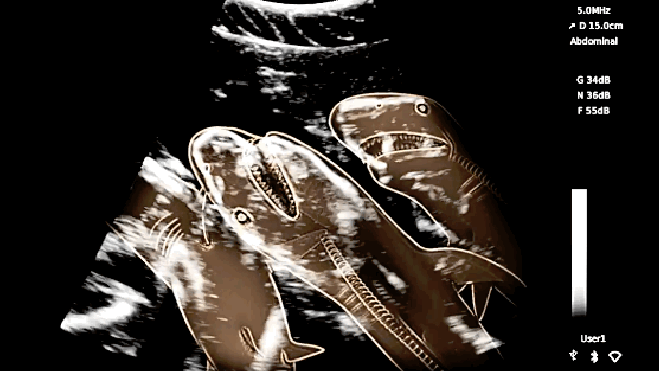

Хээл авсан амьтадын хэвлийн рентген зураг ингэж харагддаг. Хэдий итгэмээргүй ч ийм л байна.